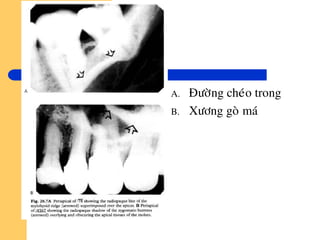

Caùc boùng caûn quang

Goàm:

 Ñöôøng cheùo trong

 Thaân xöông goø maù

 Caùc vuøng xöông xô cöùng (caùc ñaûo xöông ñaëc).

=> Laøm môø hay laøm maát boùng cuûa moâ quanh choùp.

A. Ñöôøng cheùo trong

B. Xöông goø maù